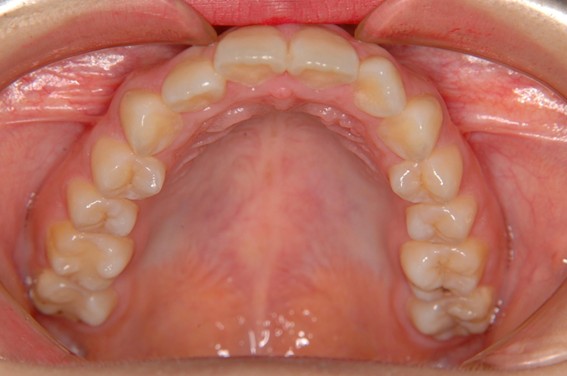

| 主訴 | 前歯が逆に噛んでいる。 |

| 治療内容 | 表側ワイヤー矯正、ジルコニア補綴を行いました。 |

| 治療費 | ワイヤー矯正660,000円(税込) ジルコニア176,000円(88,000円×2歯)(税込) |

| 治療期間 | 30ヶ月 |

| 治療回数 | 30回 |

| 想定されたリスク | 歯根吸収、歯髄壊死、歯髄充血、歯肉退縮のリスクがありました。 |

骨格性Ⅲ級・前歯部反対咬合の症例でした。反対咬合のまま治療していた前歯のサイズ不調和を、表側ワイヤー矯正とプロビジョナルクラウンで調整。正中を整え、犬歯・臼歯ともⅠ級、適切なオーバージェット(上下前歯の前後的な距離)・オーバーバイト(上下前歯の垂直的な重なり)に仕上げました。